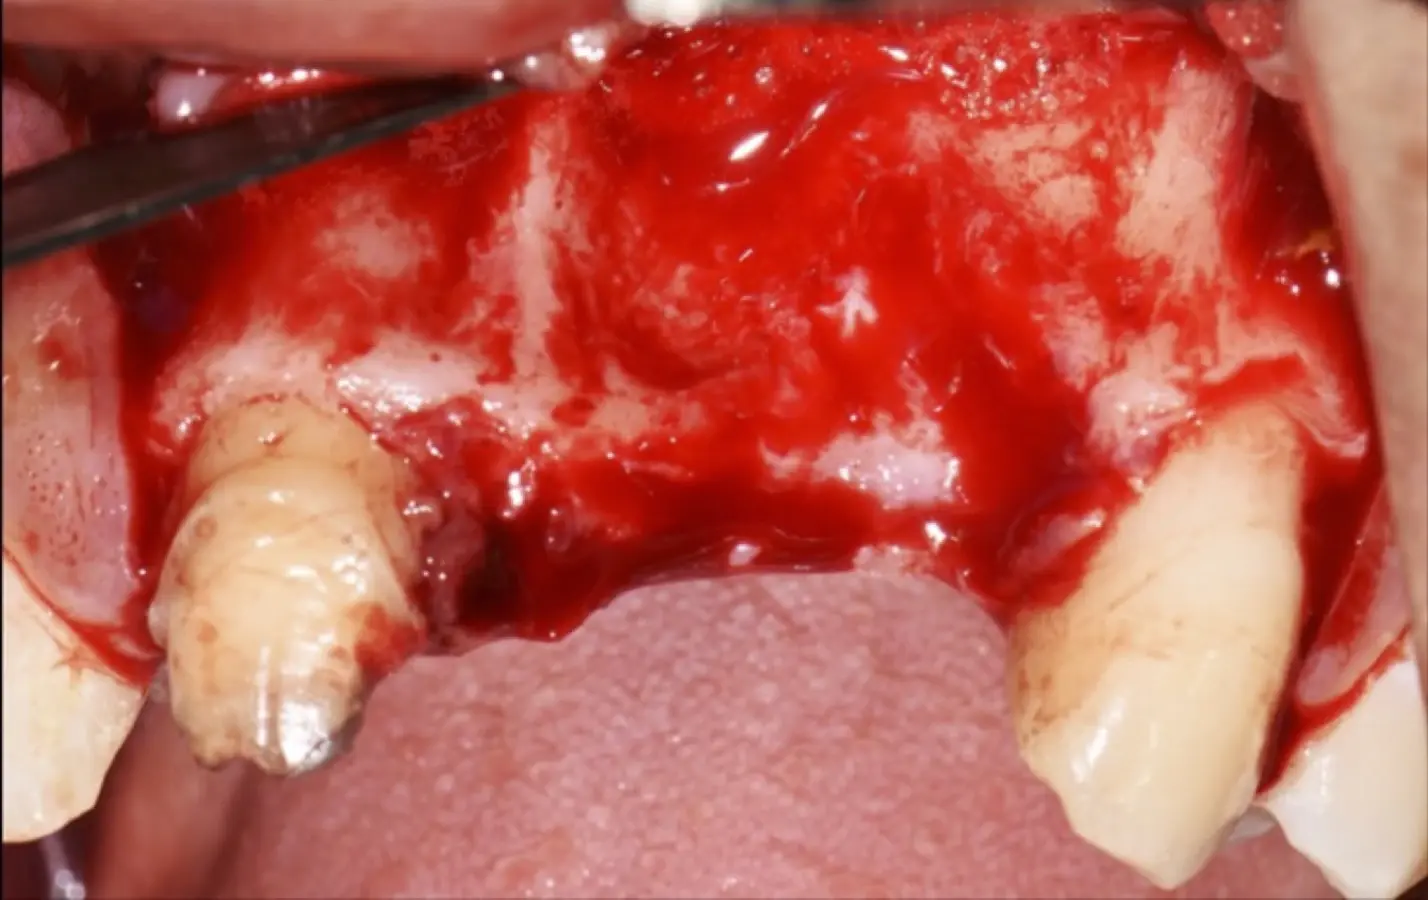

Paciente de sexo femenino de 36 años de edad, llega a la consulta por presentar una restauración protésica inadecuada. En el examen clínico se observa una restauración protésica provisional acrílica sobre las piezas 1.1 y 2.2. Adicionalmente, se aprecia recesión gingival a nivel de la pieza 2.2 y deficiencia horizontal severa de reborde a nivel de la zona edéntula correspondiente a la pieza 2.1. En la evaluación tomográfica se observa ausencia total de tabla ósea vestibular en la pieza 2.2, y se corrobora el déficit en la zona edéntula de la pieza 2.1, para lo cual se indica una reconstrucción de estructuras óseas con hueso en bloque de origen bovino y posteriormente la colocación de implantes dentales.

Figura 35. Decolado a espesor total sobrepasando la línea mucogingival (a, b).

Figura 36. Defecto óseo y severa reabsorción ósea horizontal: vista clínica (a) y corte tomográfico (b).

Figura 38. Decorticalización por medio de broca de 1.2 mm de diámetro (a, b).

Figura 39. Uso del inserto plano de punta aserrado para realizar una mayor decorticalización (a). Surcos de vascularización y nutrición (b).